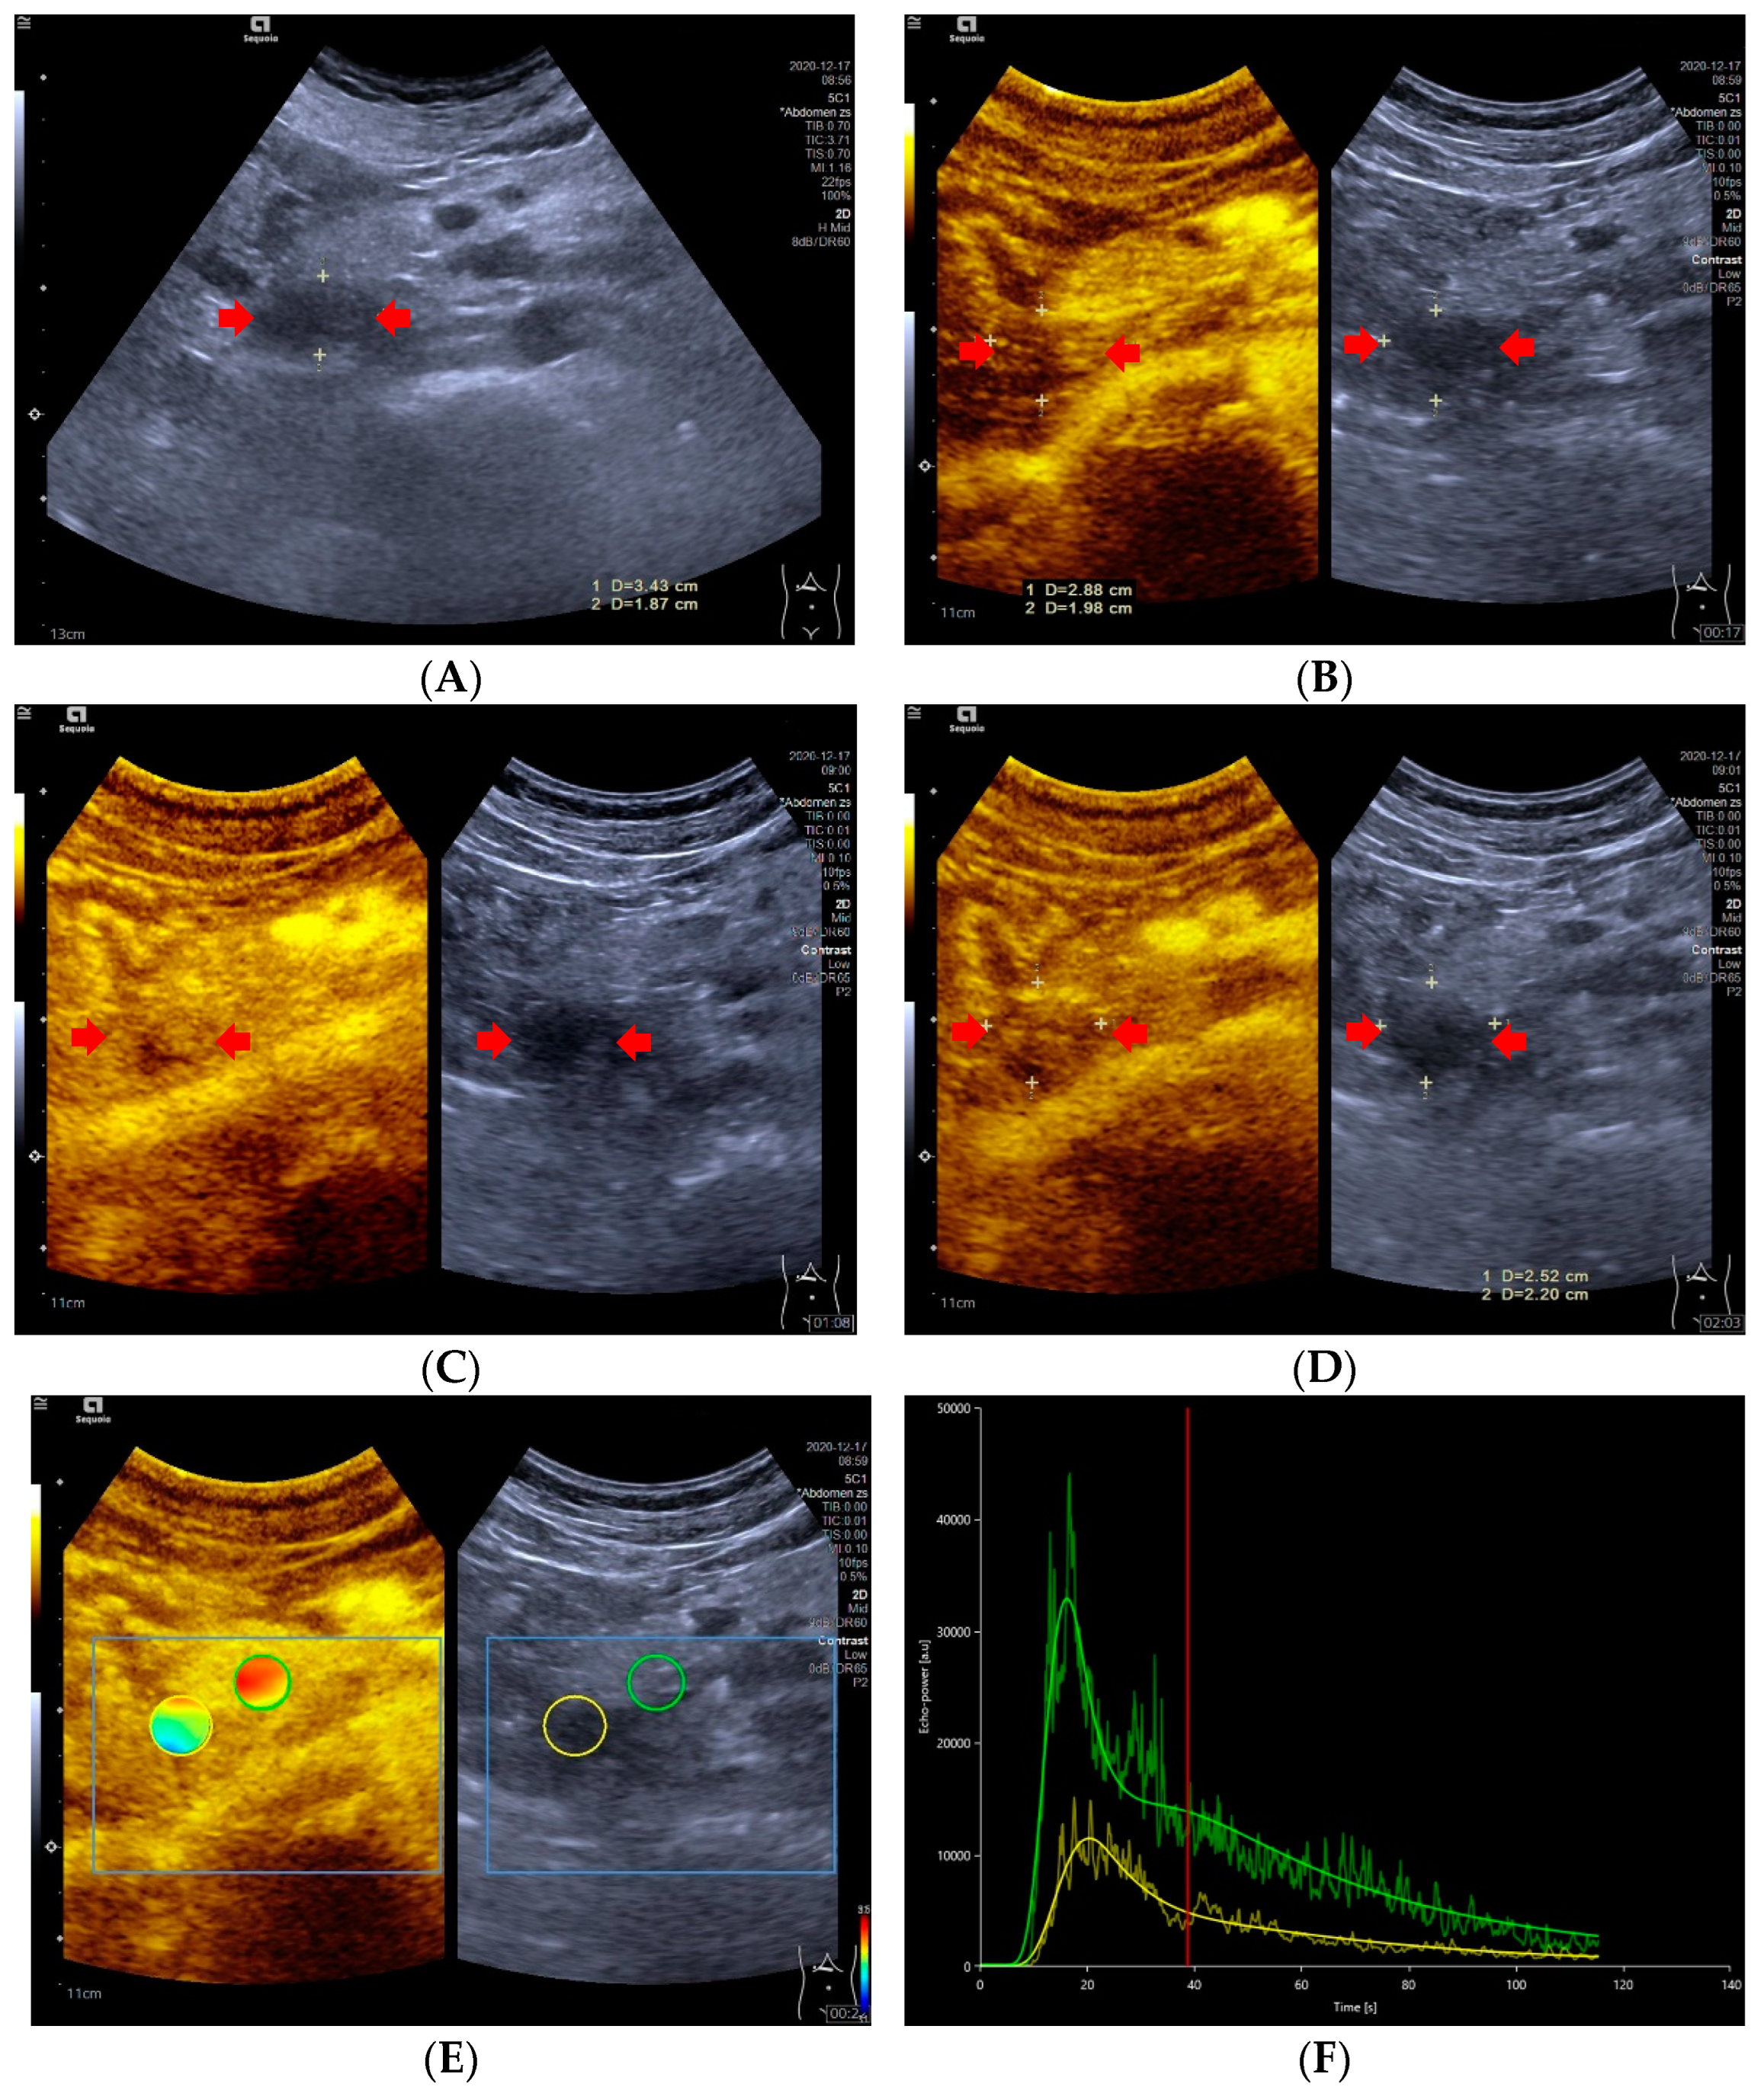

Figure 2.

A 47-year-old male with a pNECs lesion (Ki 67 proliferation index, 80%). The pancreatic head-located pNECs lesion was hypoechoic with well-defined margins (A). The pNECs lesion showed heterogeneous hypoenhancement throughout arterial phase to late phase after the contrast agent injection (B–D). The regions of interest of pNECs lesion (yellow circle) and surrounding pancreatic parenchyma (green circle) were placed manually for evaluation of the pNEC’s microvascularization utilizing external perfusion software VueBox® (E). The time intensity curve revealed that the yellow curve (pNECs lesion) was below the green curve (pancreatic parenchyma) from arterial phase to late phase (F).